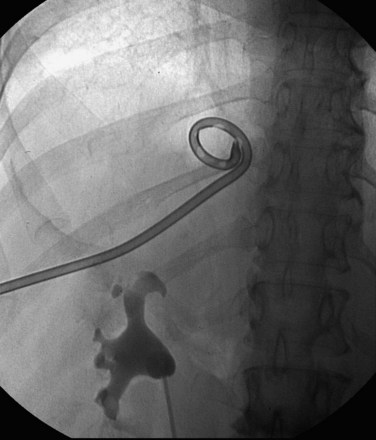

), and a guidewire can be passed from below and grasped by the nephroscope to establish through-and-through access from the external urethral meatus to the percutaneous entry site. A dual-lumen catheter can be placed as well. The small caliber of either catheter, however, does not provide much outflow from the kidney and may not prevent stone or tumor fragments from passing into the ureter along the catheter. A ureteral occlusion balloon catheter, which incorporates an approximately 15-Fr spherical balloon on the distal tip, more consistently prevents material from migrating down the ureter. The balloon should be carefully inflated in the renal pelvis, making sure the balloon is not in the ureter—which could lead to ureteral rupture—and then gently pull down to occlude the ureteropelvic junction (Fig. 47–12). Another alternative is to place a ureteral access sheath (usually 11 to 15 Fr) over a retrograde-inserted guidewire (Landman et al, 2003). The large outer diameter of the sheath effectively prevents particles from passing around the sheath into the ureter, and the large inner diameter affords excellent outflow of small stone particles. The disadvantages of employing a ureteral access sheath include the potential ureteral trauma from passing such a large device into the ureter and clogging of the catheter lumen by oversized stone fragments.

Figure 47–12 Occlusion balloon inflated and snugged down at ureteropelvic junction of contrast-filled upper tract collecting system.